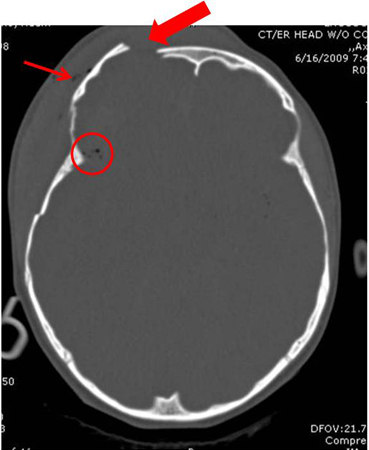

Axial CT scan demonstrating open elevated linear skull fracture (large arrow). Note the air in the soft tissues (small arrow), the small amount of pneumocephalus associated with the fracture (circle), and that the level of elevation of the bone fragment is significantly more than the thickness of the bony table

From the teaching collection of Demetrios Demetriades; used with permission